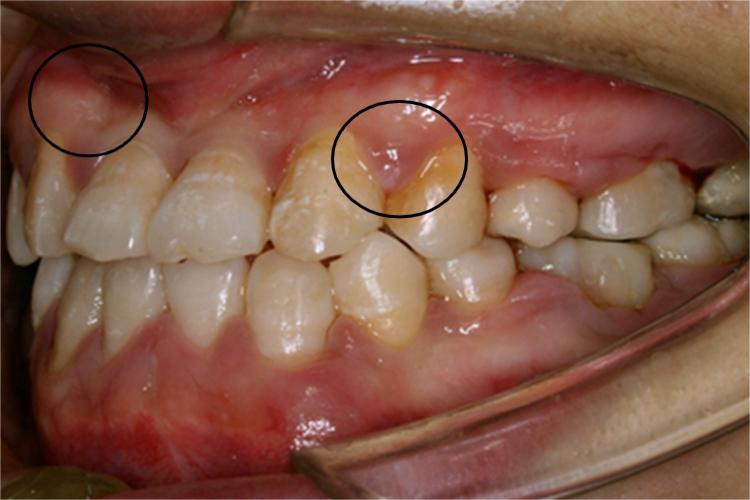

慢性牙周炎患者可出现牙龈肿的情况,开始时牙龈即出现牙周袋和牙槽骨吸收,可观察到牙龈红肿,在刷牙、进食时出血,严重时还可伴有牙齿移位、根面龋等异常。

慢性牙周炎确诊后,需要由医生清除局部致病因素,方法包括控制菌斑,彻底清除牙石,如洁治和刮治术等,以及局部药物治疗,如遵医嘱应用复方碘溶液消炎和收敛,部分患者还需要通过牙周手术、建立平衡的颌关系等措施恢复健康。